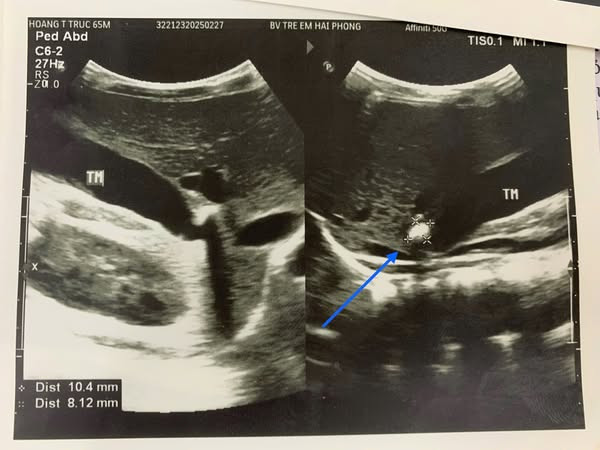

Bệnh nhân Hoàng Thanh Tr., hơn 5 tuổi vào viện vì đau bụng và nôn dịch vàng, qua khám, làm các xét nghiệm, thăm dò Chẩn đoán hình ảnh, trẻ được chẩn đoán tắc túi mật cấp do sỏi kẹt cổ túi mật, nguy cơ hoại tử túi mật. Các bác sĩ đã tiến hành phẫu thuật nội soi cắt túi mật đồng thời lấy sỏi, ca phẫu thuật diễn ra an toàn, ngay sau mổ 1 ngày đã có thể ăn uống trở lại.

| Hình ảnh sỏi túi mật trên siêu âm - Ảnh BVCC |